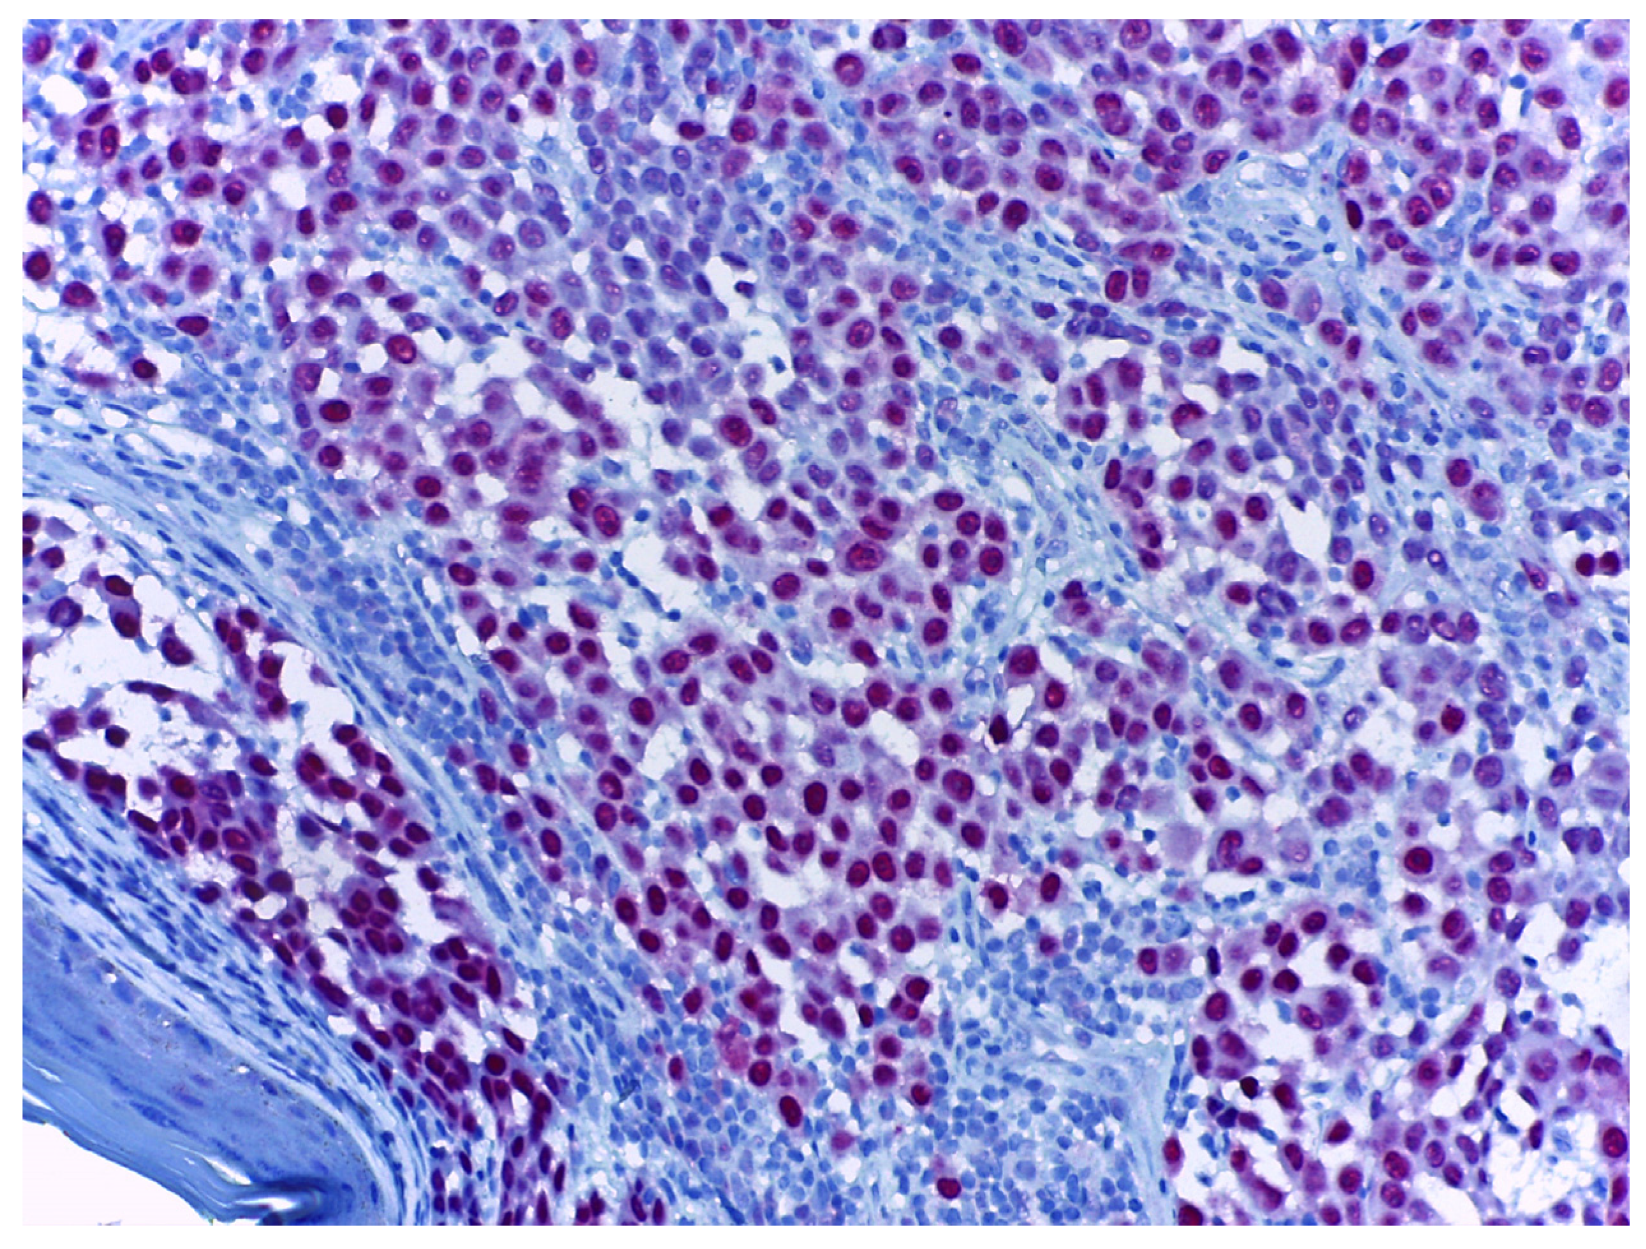

- Ronchi, A.; Cazzato, G.; Ingravallo, G.; D’Abbronzo, G.; Argenziano, G.; Moscarella, E.; Brancaccio, G.; Franco, R. PRAME Is an Effective Tool for the Diagnosis of Nevus-Associated Cutaneous Melanoma. Cancers 2024, 16, 278. [Google Scholar] [CrossRef] [PubMed]